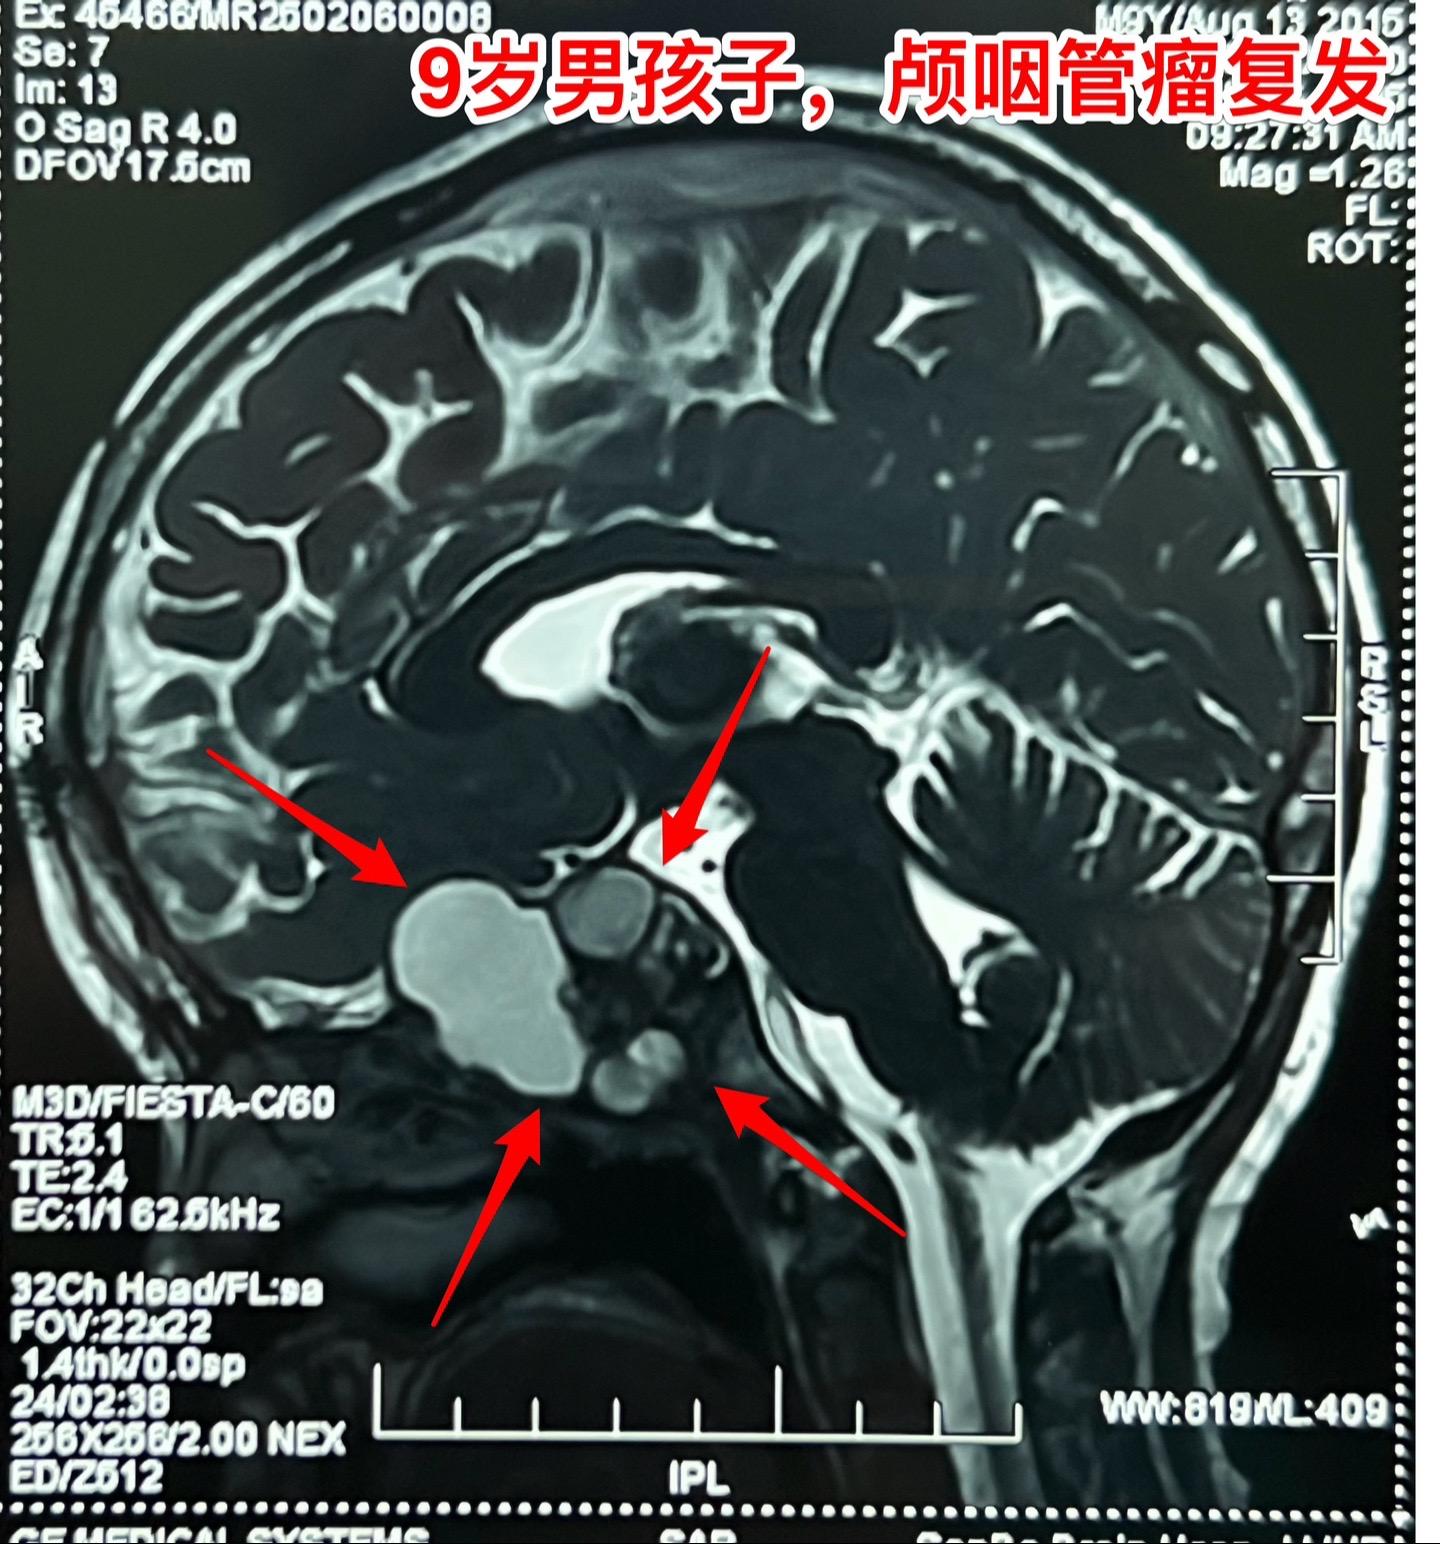

九岁男孩子颅咽管瘤复发,肿瘤生长快。南阳市男孩子2年半前曾经作了一次手术,2024年2月复查磁共振显示垂体窝内无肿瘤复发,鞍背骨质内有可疑异常信号。2025年1月复查磁共振即显示肿瘤复发而且直径达4厘米,患儿家长不敢相信肿瘤居然长得这么快!正月初八患儿即来住院,复查磁共振及CT见图。 病友们经常咨询的问题是肿瘤的生长速度。虽然颅咽管瘤是良性肿瘤,但是不能肯定地说颅咽管瘤的生长速度就很慢。即使在较长时间内肿瘤生长缓慢,也可能在某个时间段出现快速生长,也就是说颅咽管瘤的生长速度不是匀速的,难以预